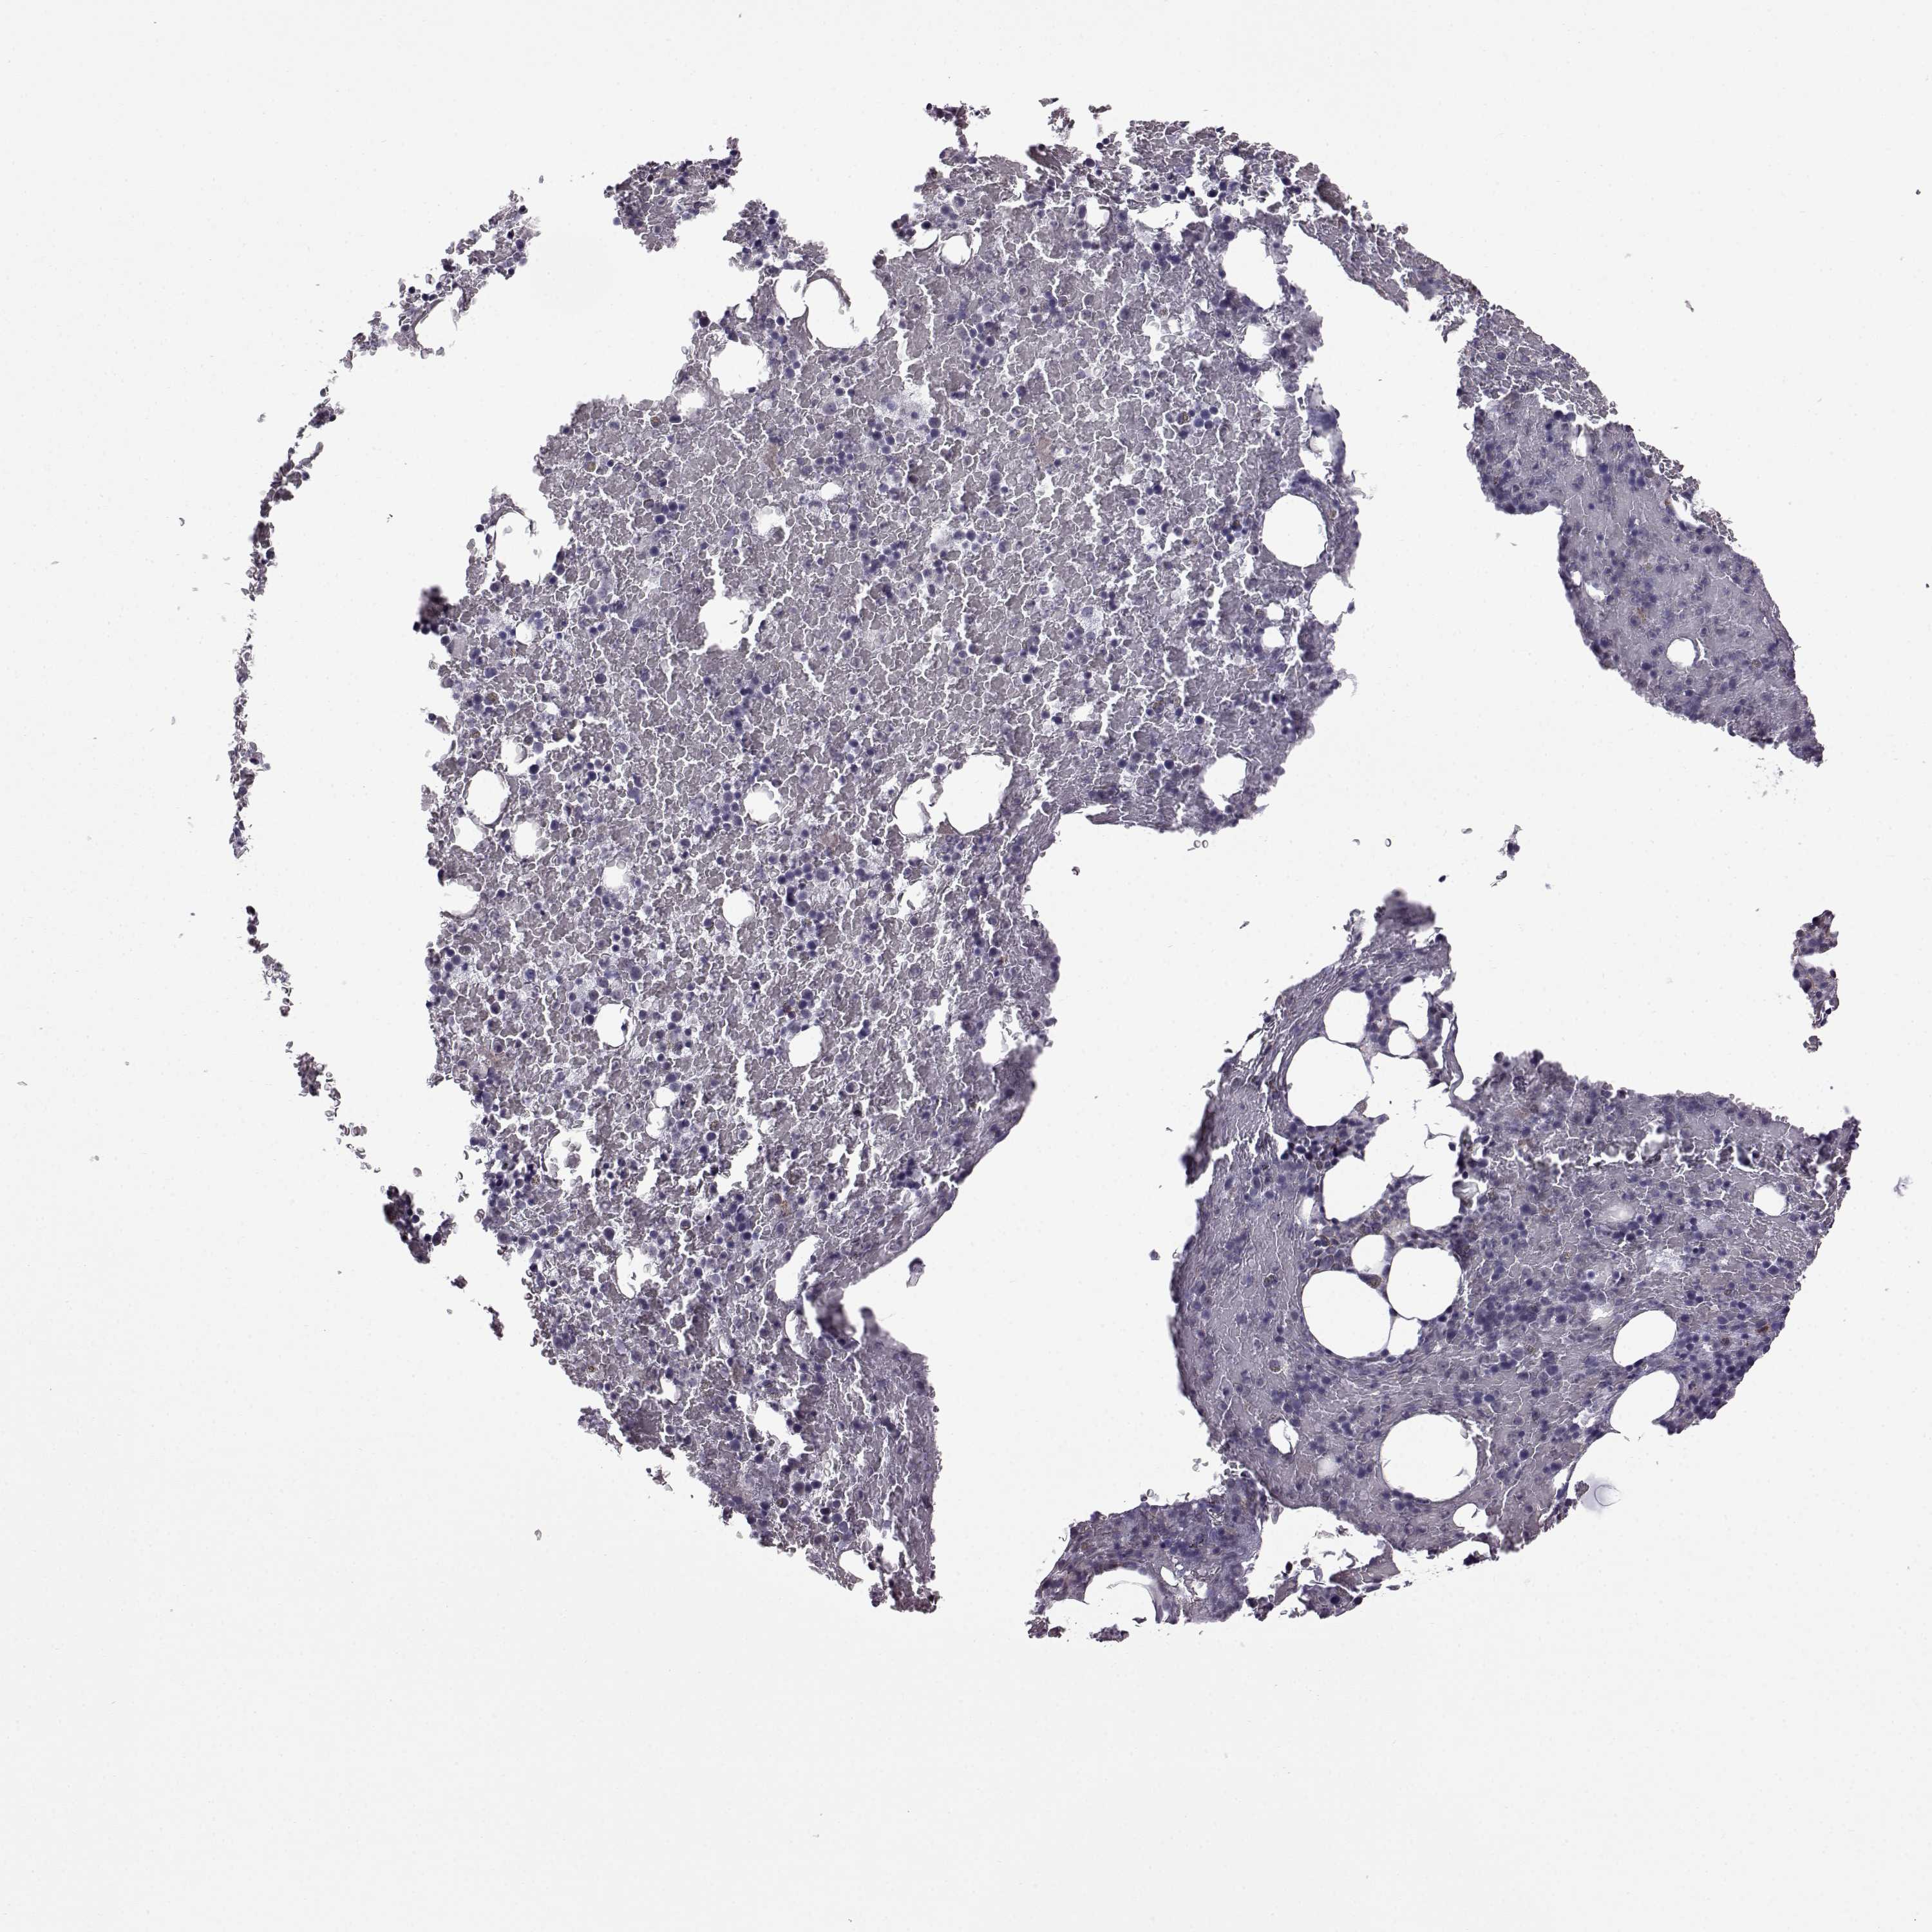

BONE MARROW - Antibody stainingi

Antibody staining in the annotated cell types in the current human tissue is reported as not detected, low, medium, or high, based on conventional immunohistochemistry profiling in selected tissues. This score is based on the combination of the staining intensity and fraction of stained cells. Each image is clickable and will lead to virtual microscopy that enables deeper exploration of all samples and also displays staining intensity scores, fraction scores and subcellular localization as well as patient and tissue information for each sample.

Antibody HPA030665Antibody HPA068563Antibody CAB037231

Hematopoietic cells Not detectedNot detectedNot detected

Male, age 68

Bone marrow sample 98

nTPM: 0.3

Cell types%

Myelopoietic cells:

50

Erythropoietic cells:

30

Lymphocytes:

10

Monocytes:

5

Blastic cells: